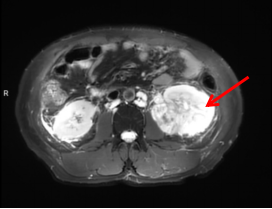

图1 术前MR提示左肾巨大占位